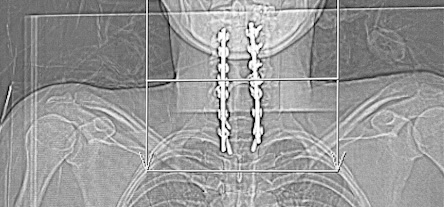

My cervical spine x-ray

After my crash, the goal was to decompress the spinal cord and stabilize my neck. Surgeons performed a posterior laminectomy—removing the lamina, the bony roof over the spinal canal—to give the cord more room. Then they stabilized my spine with rods and screws in a fusion from C3 down to T3. Fusion means those vertebrae are now joined so they no longer move, protecting the cord while it heals.